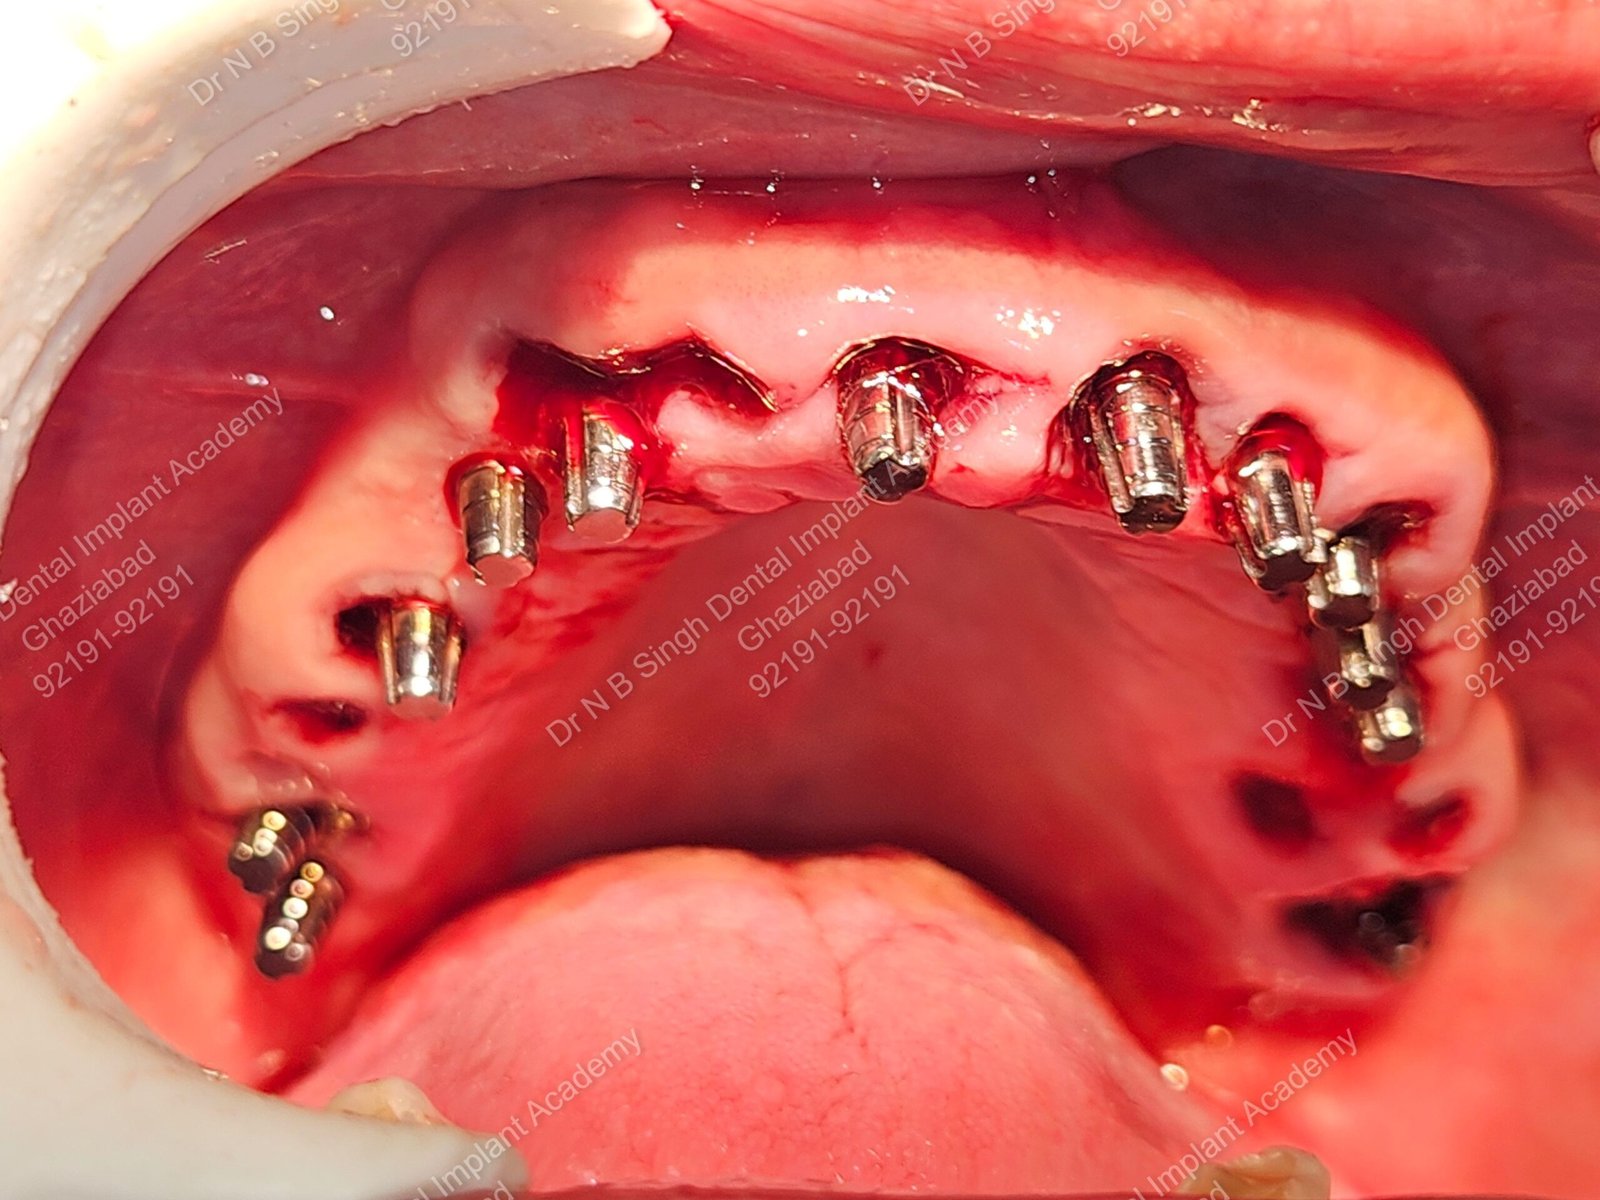

1006 Basal implant full mouth-DEEPAK